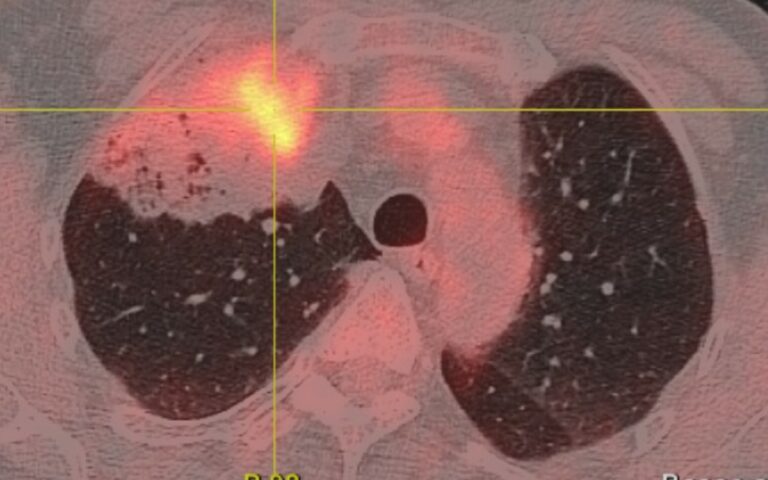

Le dépistage s’appuie sur un scanner thoracique à faible dose d’irradiation. Cet examen permet d’identifier des nodules pulmonaires de petite taille, souvent opérables. Plus un cancer du poumon est diagnostiqué tôt, plus les chances de survie augmentent significativement.

• Intelligence artificielle appliquée à l’imagerie radiologique